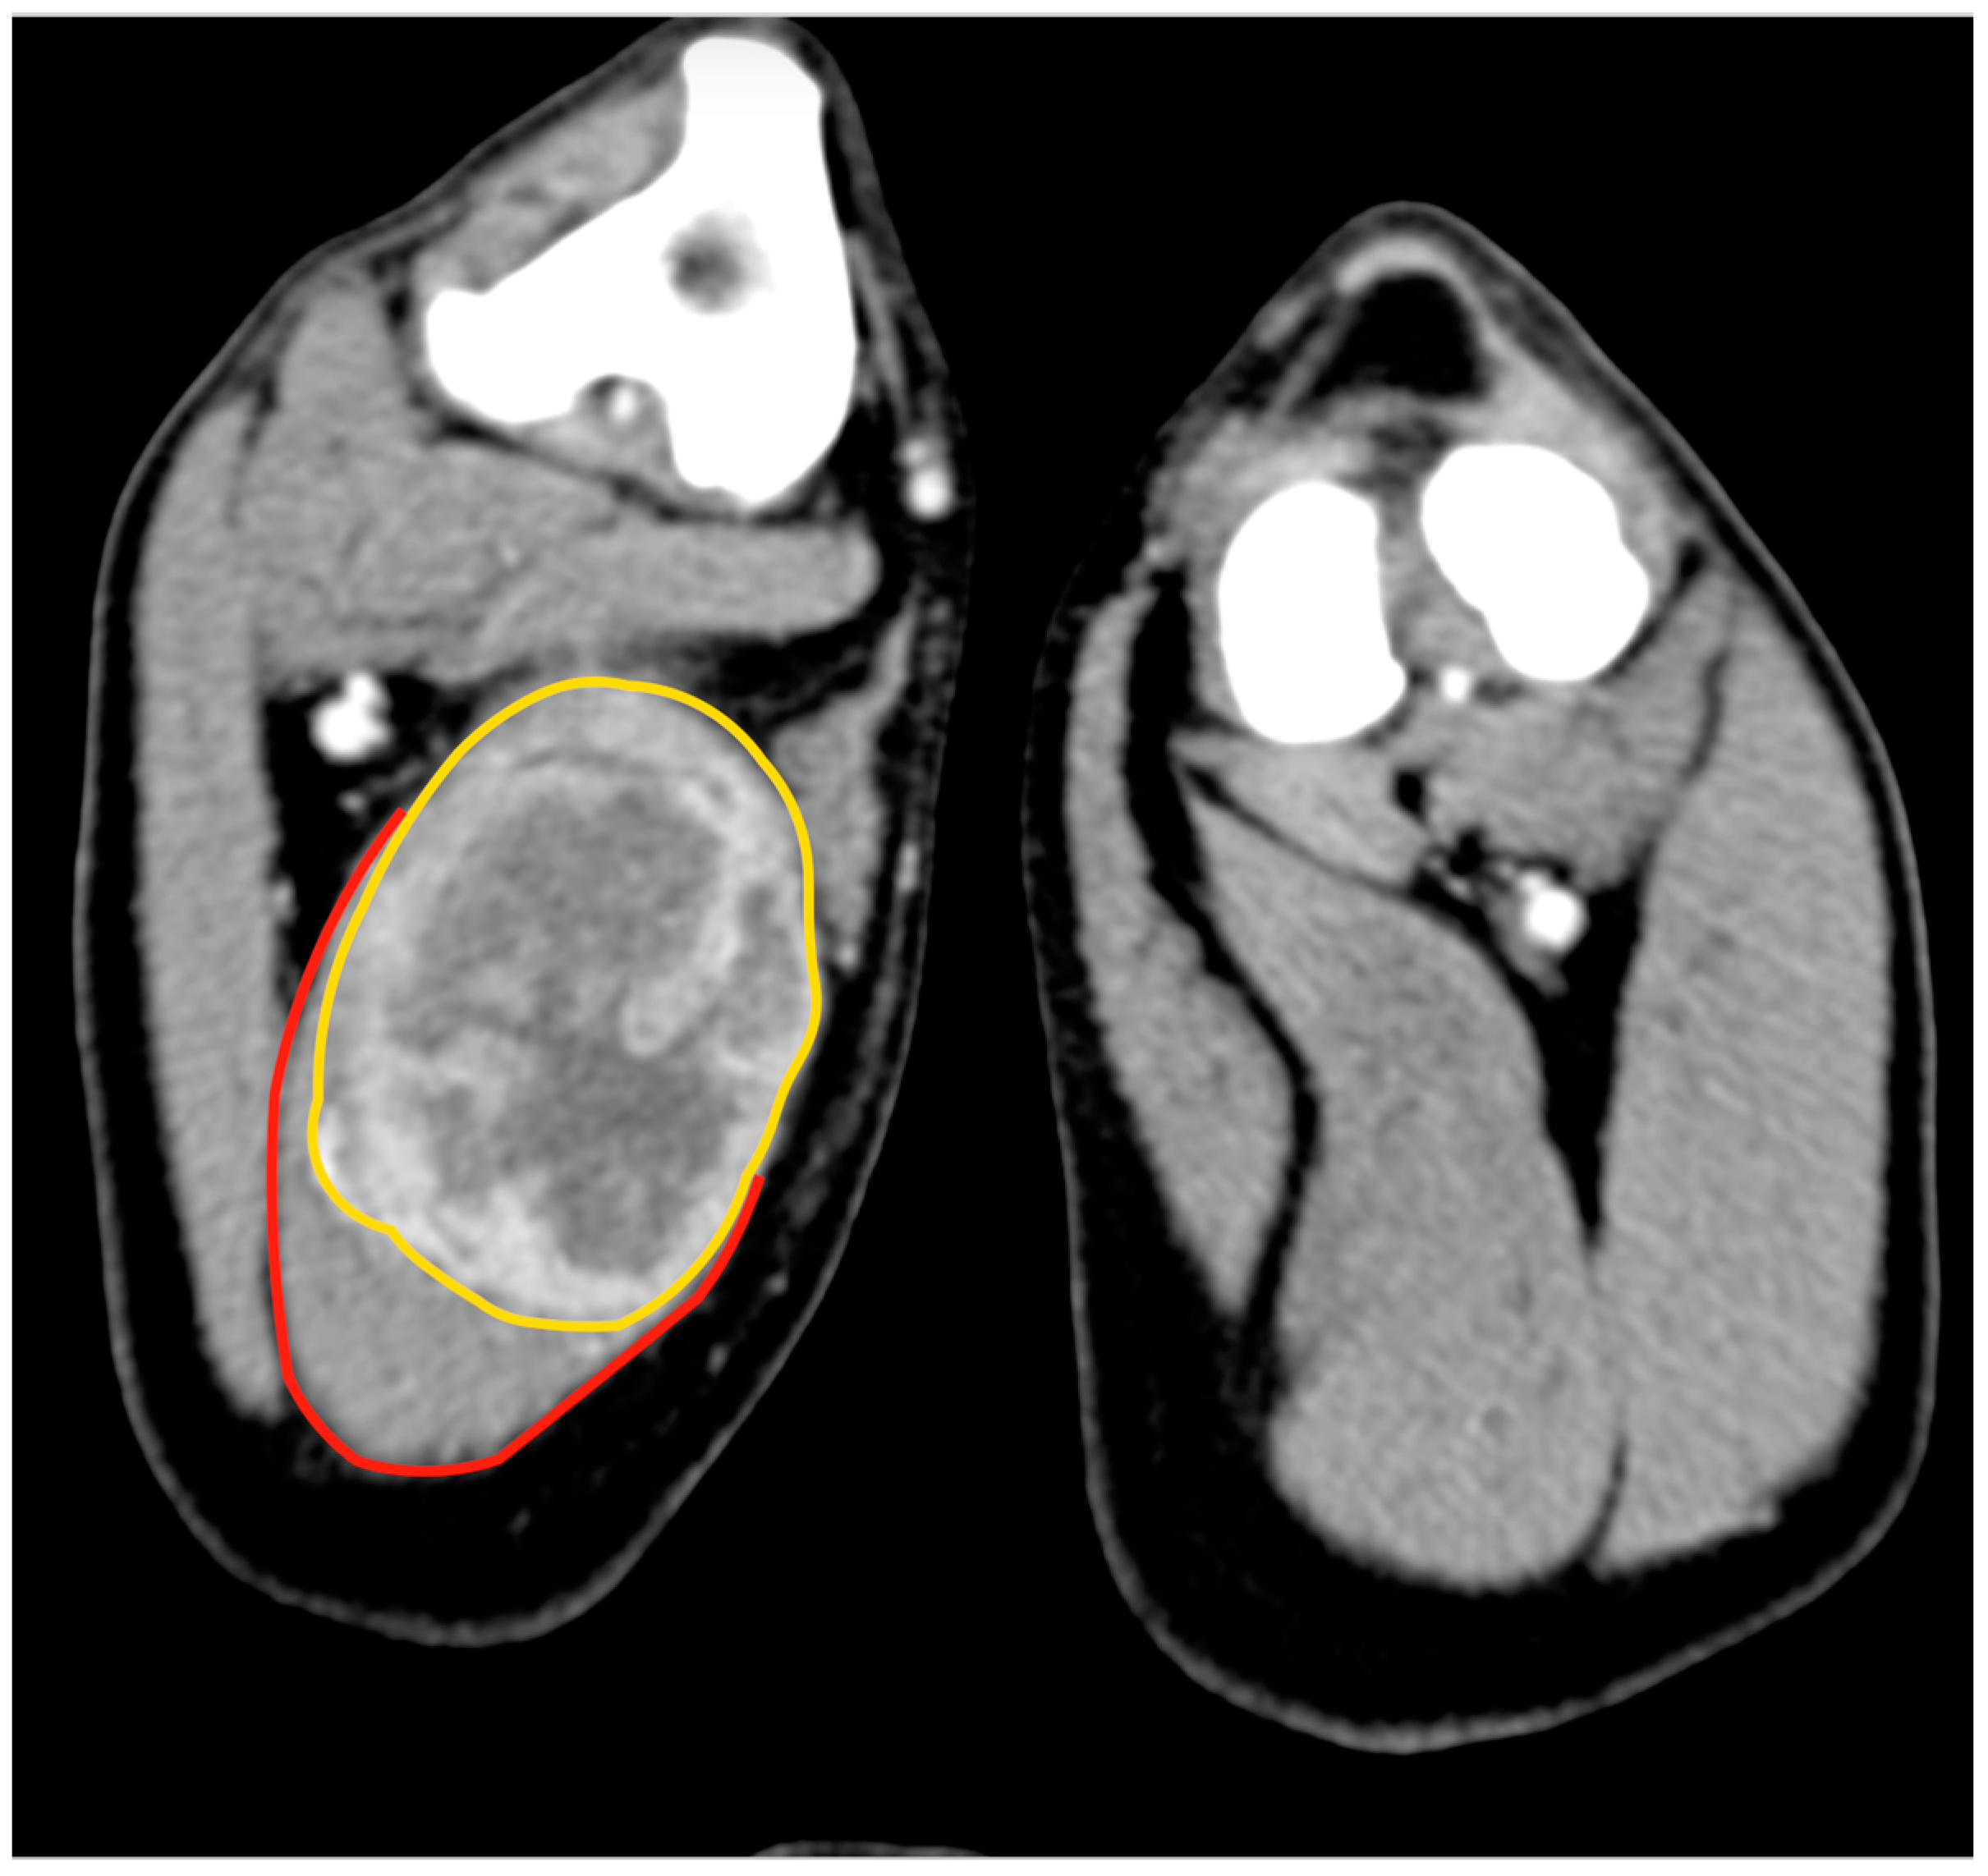

Animals Free Full Text Surgical Excision Of Intramuscular Sarcomas